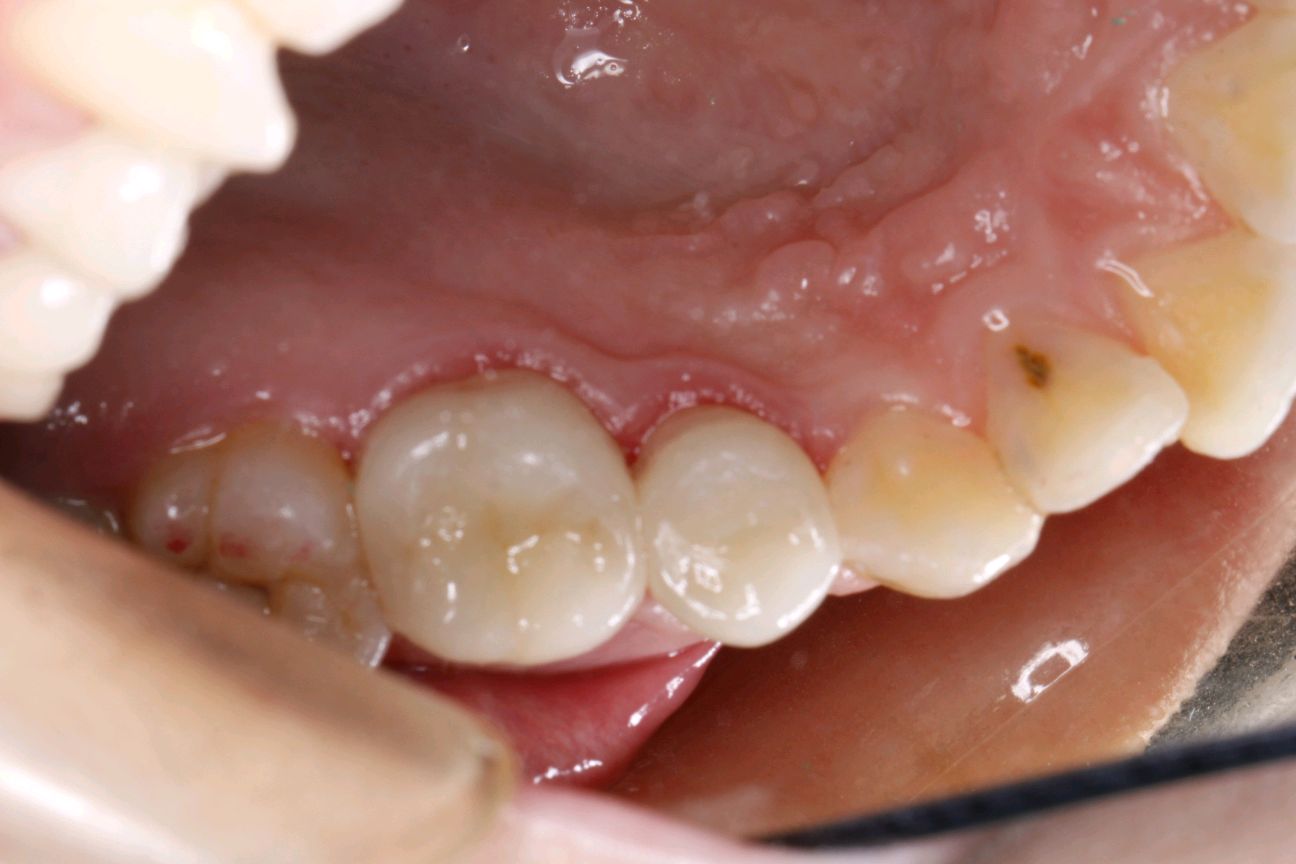

治疗计划:根管治疗+纤维桩+高嵌体修复

术后